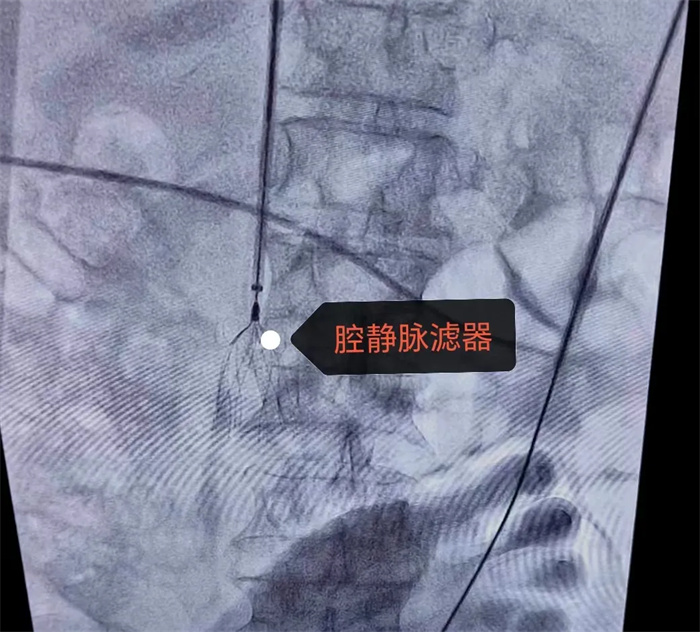

植入下腔靜脈濾器

朱永彪主任與科室手術(shù)介入團(tuán)隊(duì)制訂詳細(xì)的手術(shù)方案后,決定予患者實(shí)施下腔靜脈濾器植入+下肢深靜脈血栓接觸性溶栓、機(jī)械血栓抽吸+必要時(shí)球囊擴(kuò)張成形術(shù)。

因患者術(shù)中造影顯示:左側(cè)髂靜脈閉塞,故手術(shù)采用左側(cè)腋靜脈入路,經(jīng)造影確定在雙腎靜脈開口下方植入腔靜脈濾器;再通過導(dǎo)絲導(dǎo)管交換技術(shù),行右下肢靜脈造影見腘靜脈、股淺靜脈、股總靜脈、髂外靜脈、髂總靜脈內(nèi)大量充盈缺損,血流速度緩慢。